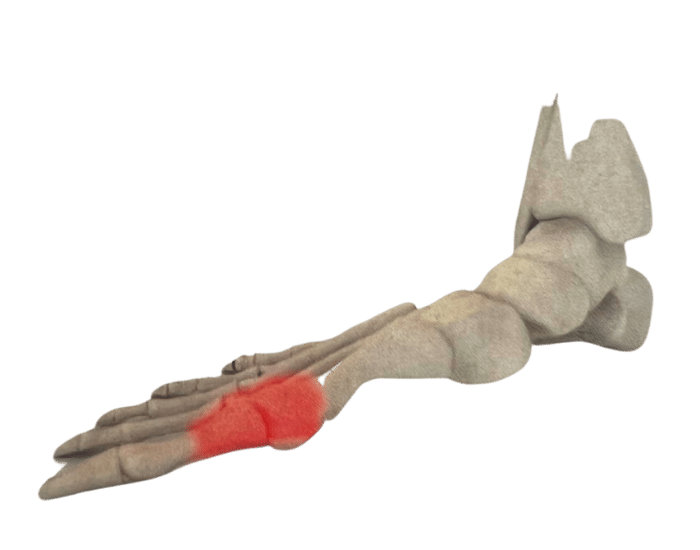

There are numerous reasons why you might need Custom Foot Orthotics. If you have pain in your foot, heel, knee or hip, have high arches or flat feet; or just being regularly on your feet and are getting any aches or pains in the feet or legs, or suffering from general foot pain while walking, running, playing sports or even at rest you qualify for Custom Foot Orthotics.